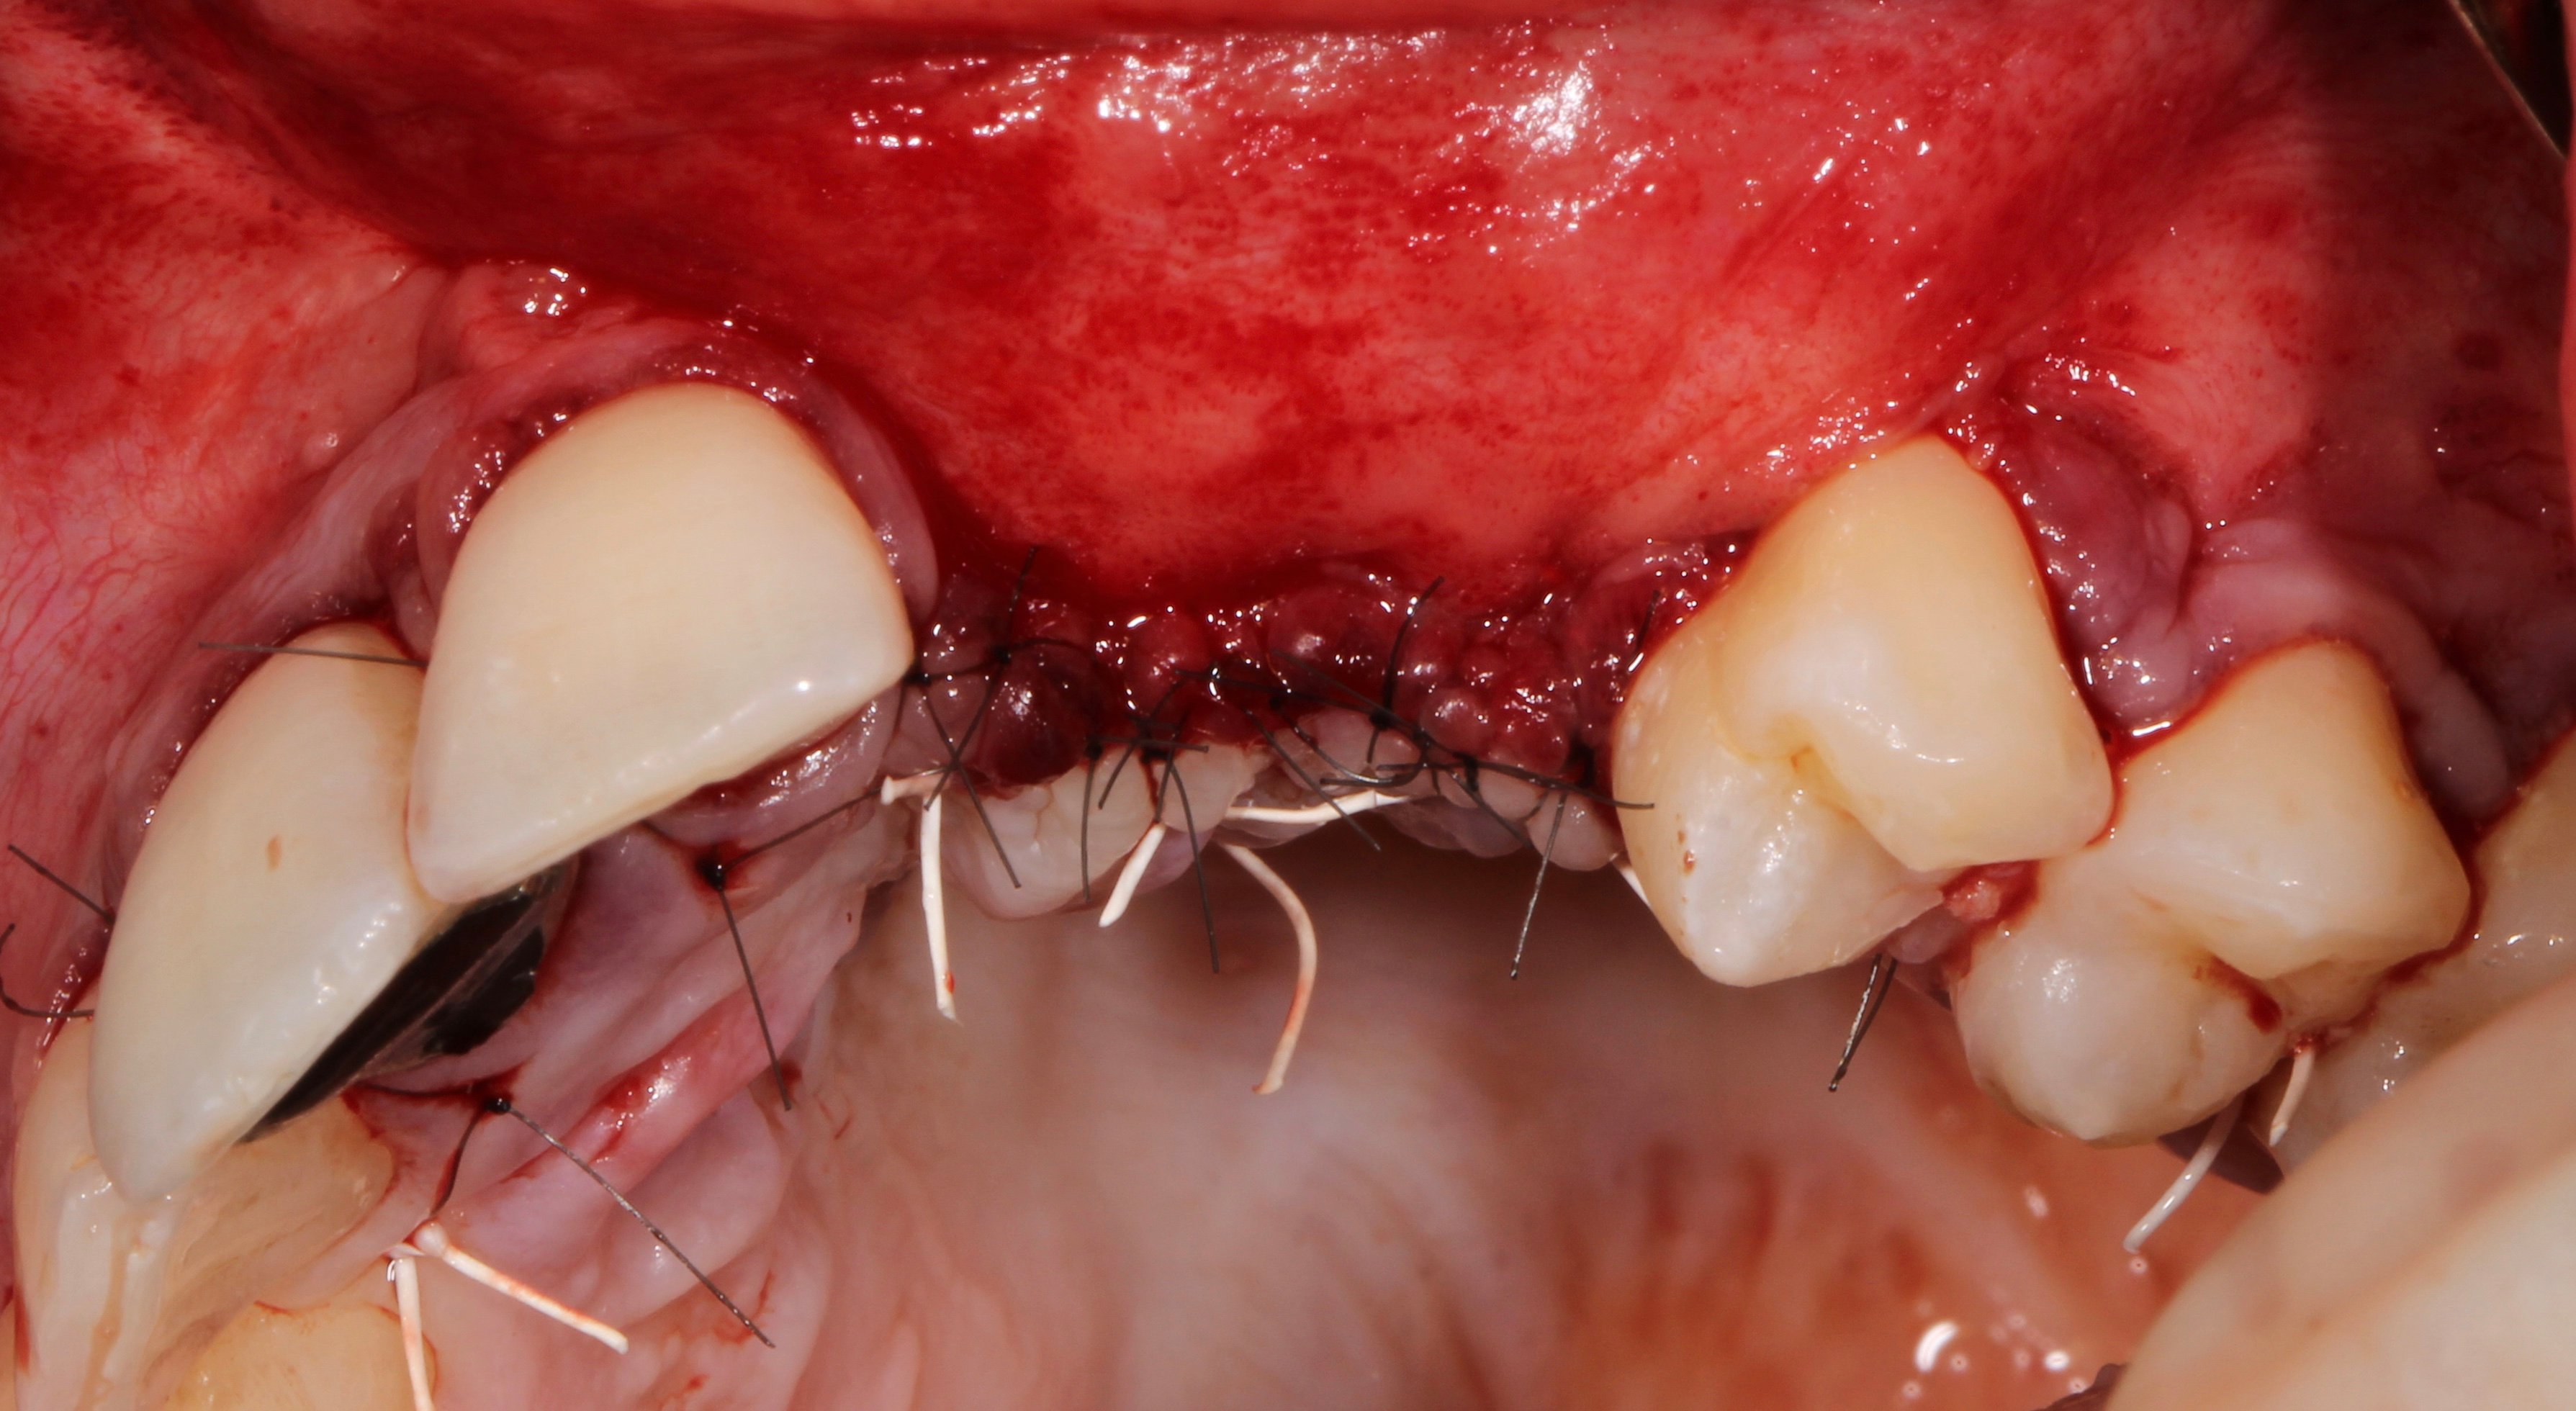

- 3 months later: (which turned out to be 2 years later because the patients was treated and failed elsewhere): 3D guided bone regeneration using 100% autogenous bone and a PTFE, Ti-reinforced NeoGen® membrane which was fixed by Neoss Tacks.